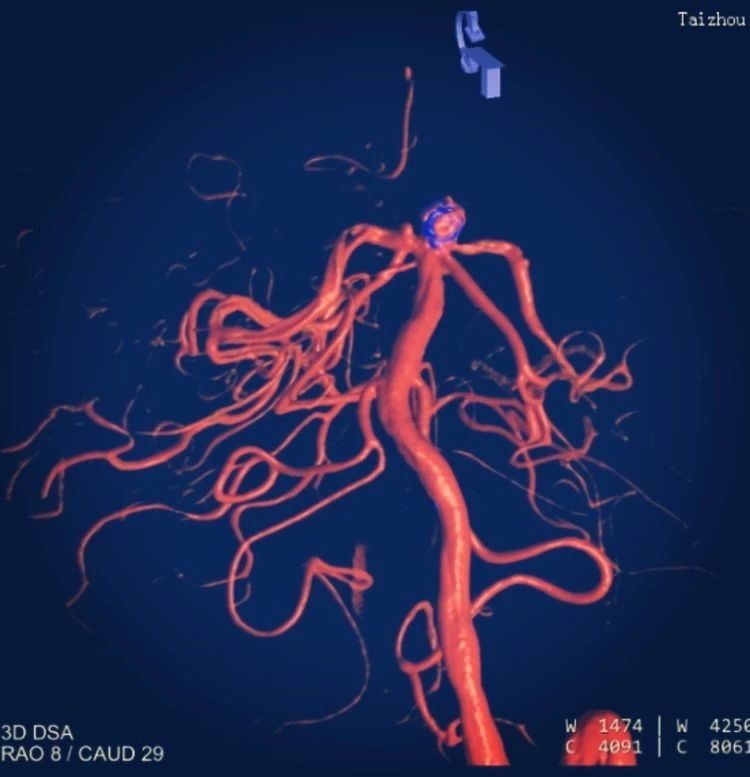

術(shù)中影像重建顯示的不同角度的動脈瘤,看起來很漂亮哦